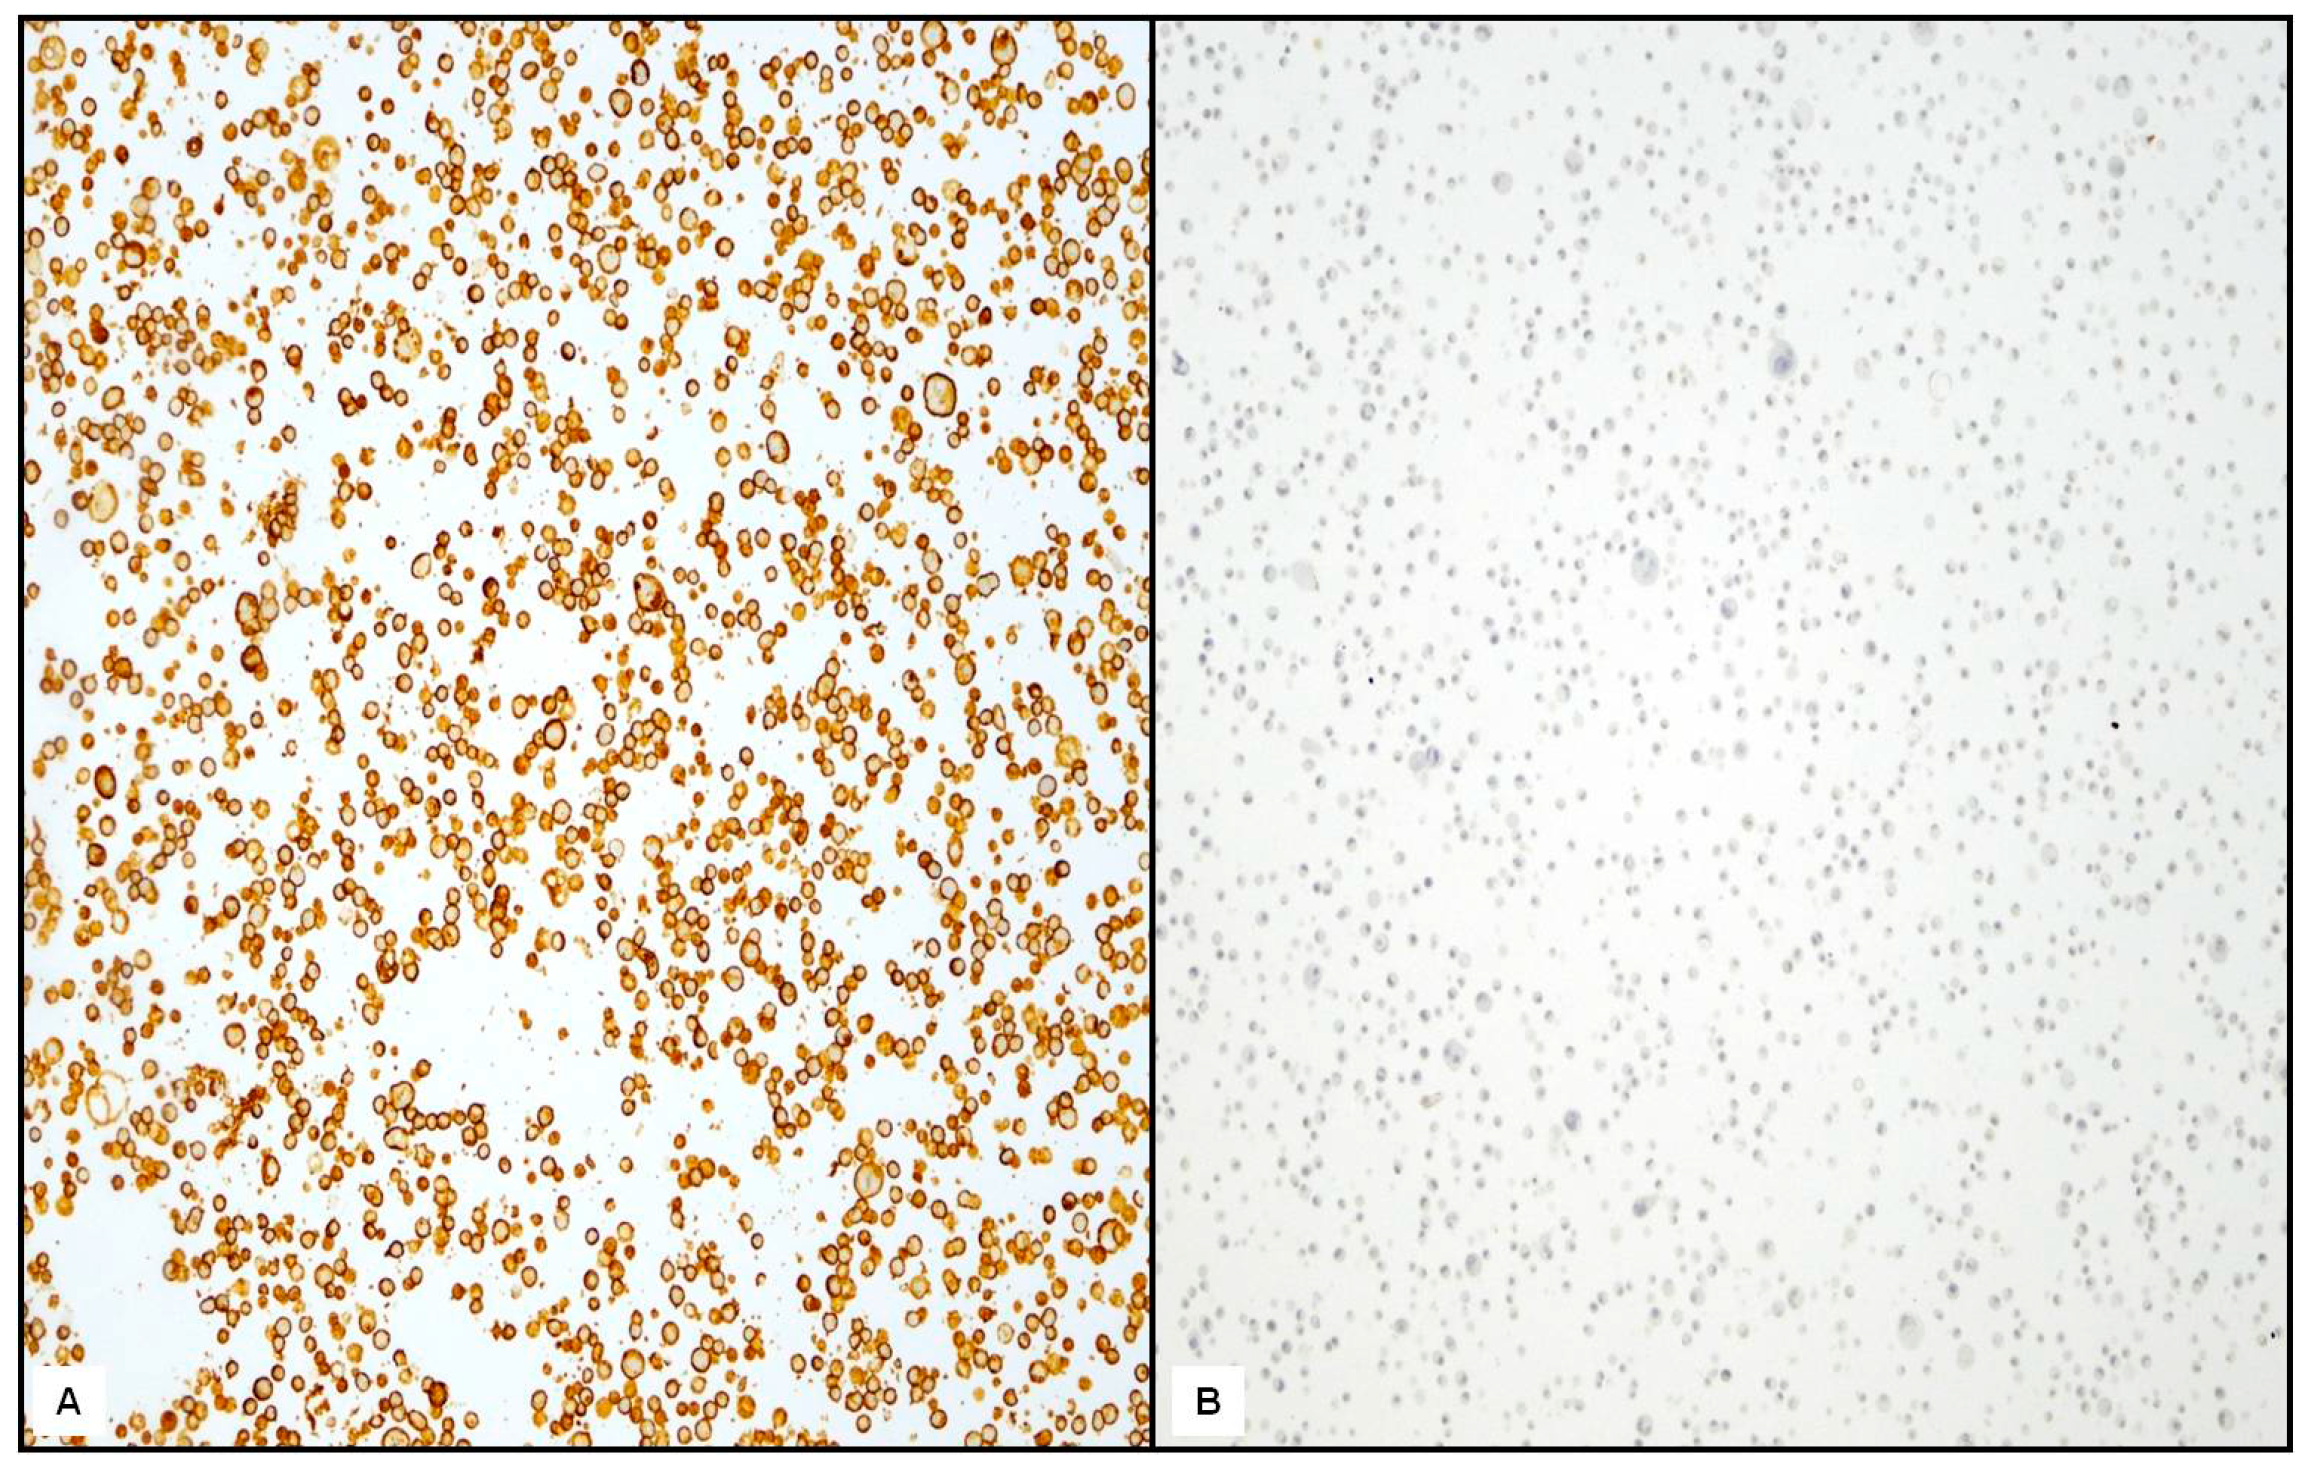

| IHC Negative/low (0, 1+) | 12 (26.6%) | 30 (66.6%) | 0.020 |

| Equivocal (2+) | 15 | 7 | |

| Positive (3+) | 18 | 8 | |

| IHC/FISH | |||

| Positive cases | |||

| (3+ and amplified) | 20 (44.4%) | 8 (17.7%) | 0.046 |